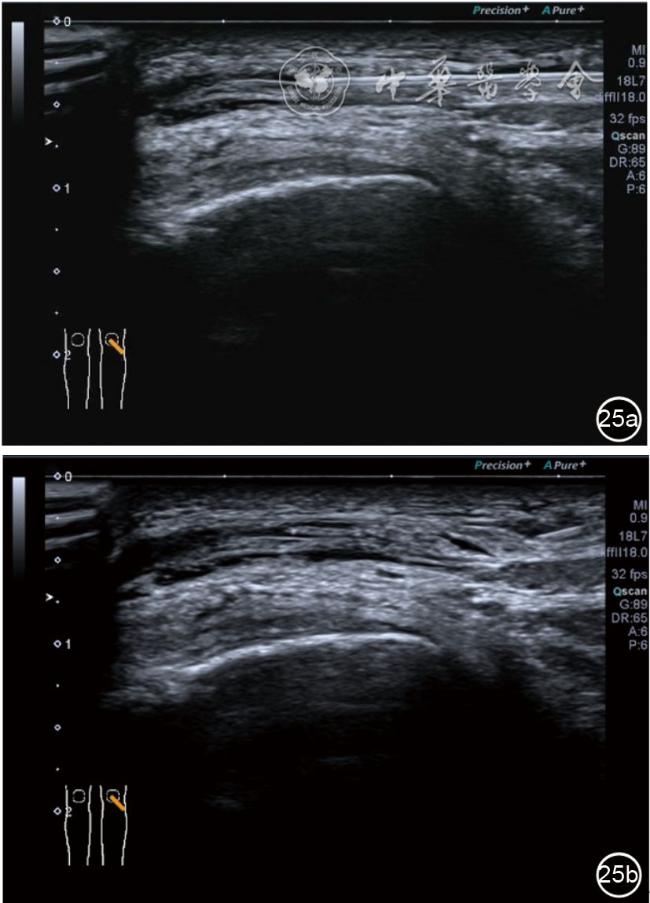

2.膝关节静态结构治疗。动力平衡失调后,继发静态结构变化,出现内外侧副韧带、交叉韧带、脂肪垫、半月板等结构变化。这里介绍半月板与交叉韧带的处理。(1)膝关节静态结构半月板治疗。在膝关节骨关节炎中主要是突出和损伤。突出主要发生于膝内翻引起的内侧半月板突出,引起内侧副韧带的张力增高。内侧半月板与内侧副韧带相连,是引起膝关节内侧疼痛的主要原因之一。治疗主要是针刀剥离松解,部分损伤可行PRP注射。①半月板突出针刀剥离松解治疗。针刀治疗主要是松解和减压,缓解疼痛,不能复位。以内侧半月板突出治疗为例。患者平卧位,髋轻度外展外旋,膝关节屈曲30°,膝下垫一软枕。选用10 MHz超声探头,穿刺区域常规消毒,探头涂抹耦合剂后套入无菌手套碘伏消毒或使用无菌耦合剂。将探头置于患者皮肤表面,内侧关节间隙长轴扫查,找到半月板突出最高点,用25G针头,抽吸1%利多卡因3 ml逐层麻醉直到半月板。选用直径1 mm的Ⅰ型2号针刀从头侧向足侧方向在内侧副韧带与半月板之间,以及半月板内部进行剥离松解3~5刀拔出针刀(图13),局部压迫5分钟,无菌敷料覆盖。②半月板损伤PRP注射治疗。半月板损伤主要表现为髌下痛,伸膝加重,查体在髌下髌韧带与侧副韧带之间,沿关节间隙有固定或局限性压痛,伸膝过程中尤为明显。MRI可示半月板断裂、损伤。如果出现绞索,严重影响功能需手术治疗。半月板损伤治疗,以注射PRP修复为主。以内侧半月板后角损伤为例。患者俯卧位,治疗前准备同半月板突出针刀剥离松解治疗。选用25G注射针头,抽取1%利多卡因2 ml局部麻醉后,制取1.5 ml PRP,穿刺到达半月板撕裂处注射,注射完毕后出针(图14),局部压迫2分钟,无菌敷料覆盖。(2)膝关节静态结构交叉韧带治疗。膝关节骨关节炎交叉韧带损伤多为部分损伤,治疗早期主要为药物或PRP注射,效果不佳时针刀做止点松解。①后交叉韧带损伤药物注射治疗。主要治疗韧带肿胀、无明显断裂患者。患者俯卧位,膝关节伸直位。一般选用10 MHz超声探头,治疗前准备同半月板突出针刀剥离松解治疗。将探头置于患者皮肤表面,后交叉韧带长轴扫查,找到胫骨止点,选用22G长针头,抽吸1%利多卡因3 ml+曲安奈德10 mg,从头侧向足侧方向穿刺到后交叉韧带胫骨止点部位的韧带表面进行注射,注射结束拔出针头(图15),局部压迫2分钟,无菌敷料覆盖。②前交叉韧带损伤PRP注射治疗。患者仰卧位,膝关节伸直。选用10 MHz超声探头,治疗前准备同半月板突出针刀剥离松解治疗。将探头置于患者皮肤表面,短轴扫查,找到前交叉韧带胫骨止点,选用25G针头,抽吸1%利多卡因3 ml逐层麻醉直到韧带止点部位,制备PRP 3 ml注射到前交叉韧带显露部位,注射结束拔出针头(图16),局部压迫2分钟,无菌敷料覆盖。③前交叉韧带损伤针刀剥离松解治疗。体位与治疗前准备同前交叉韧带损伤PRP注射治疗。短轴扫查找到前交叉韧带胫骨止点,选用25G针头,抽吸1%利多卡因3 ml逐层麻醉直到韧带止点部位,选用直径0.6 mm的Ⅰ型2号针刀从外侧向内侧于前交叉韧带胫骨止点部位剥离松解3~5刀拔出针刀(图17),局部压迫5分钟,无菌敷料覆盖。

图13 超声引导下半月板突出针刀剥离松解治疗